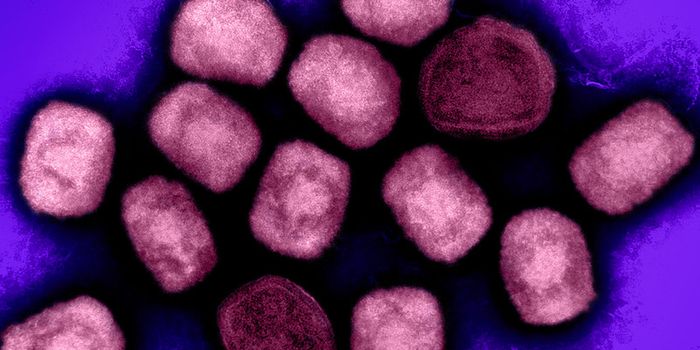

DEC 31, 2024Clinical & Molecular DXIn late November 2024, the World Health Organization was alerted to a serious public health crisis in a region of the Co ...